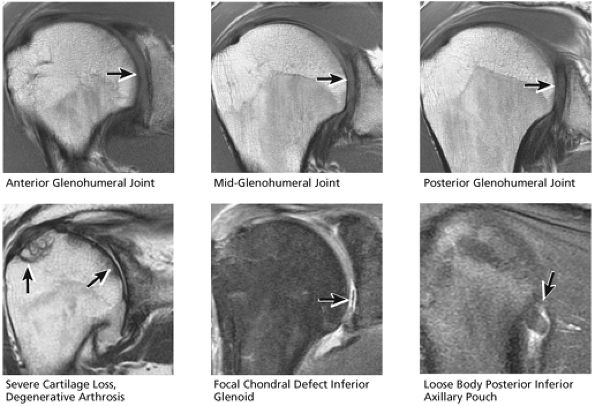

FIGURE 8.32 Rotator Cuff.

FIGURE 8.33 Acromioclavicular Joint.

FIGURE 8.34 Biceps Tendon.

FIGURE 8.35 Labrum.

FIGURE 8.36 IGL.

FIGURE 8.37 Glenohumeral Joint.

FIGURE 8.38 Osseous.

FIGURE 8.39 Deltoid Muscle.